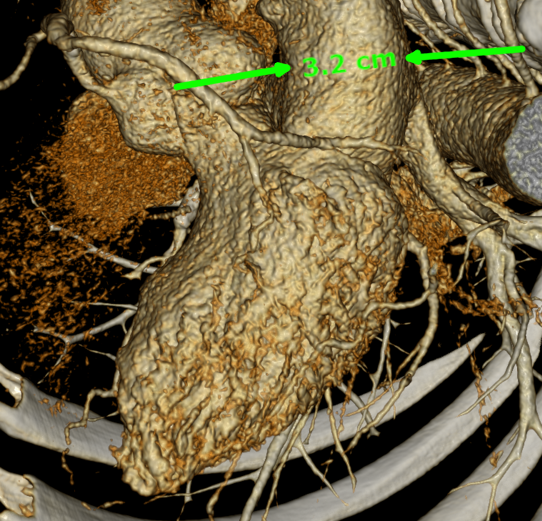

На рисунке ниже изображена трехмерная реконструкция сердца, полученная в результате работы современного томографа:

Для масштаба указана толщина луковицы аорты — 3.2 см, подумать только! Однако, когда у людей возникают проблемы с сердцем из-за сосудов, то речь, как правило, идет вовсе не о таких больших. На изображении видно, что сердце окружено более мелкими сосудами, и некоторые из них ответвляются прямо из крупных артерий. Это так называемые коронарные артерии, которые питают кровью непосредственно сердце. Если в них происходит сужение просвета (стеноз), например, из-за образования кальция, то уменьшается поток крови. Когда стеноз ярко выражен, то случается некроз ткани, другими словами инфаркт. Далее я расскажу о нашем подходе к вычислению границ сосудов, который в результате позволяет автоматически находить сужения и давать им оценку.